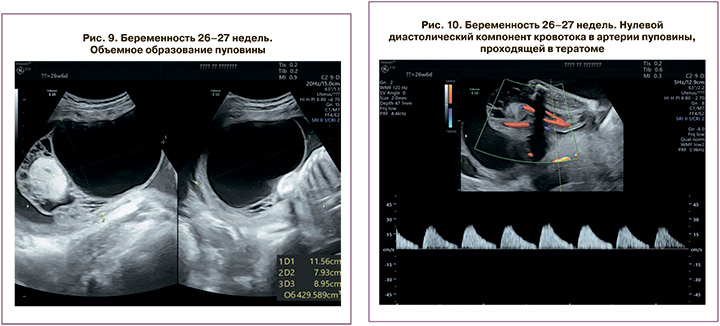

При гестационном сроке 26 недель 6 дней размеры плода соответствовали 24 неделям беременности; предполагаемая масса 660 г (менее 1 перцентиля) Диаметр свободного участка пуповины 12–13 мм. На протяжении пуповины определялось кистозное образование общими размерами 115×79×85 мм, объем – 420 cм3 (рис. 9). В структуре образования – киста 78×58×80 мм, объем – 194 cм3, тонкостенная, анэхогенная; ячеистое образование по типу отека вартонова студня размером 46×31 мм и гиперэхогенный фрагмент, возможно, тератома, размерами 33×26×29 мм, объем – 14 cм3. Топография сосудов пуповины относительно тератомы прежняя. Допплерография: частота сердечных сокращений – 133 в 1 минуту. Артерия пуповины в толще солидного образования – тератомы: СДО – 7,4, ПИ – 1,55 (более 95 перцентилей) с эпизодами нулевого кровотока в диастолу (рис. 10). Артерия пуповины, проходящая по краю образования: СДО – 3,22, ПИ – 1,11 (50 перцентилей). Артерии пуповины (на свободном участке): СДО – 4,0, ПИ – 1,27 (менее 95 перцентилей). Средняя мозговая артерия: ПИ – 1,54. Заключение: беременность 26–27 недель. Головное предлежание. Ранняя ЗРП. Объемное образование пуповины (вероятнее – кистозная тератома). Гемодинамические нарушения в артериях пуповины с критическими значениями диастолического кровотока в одной из артерий.

С учетом высокого риска антенатальной гибели плода пациентка направлена в перинатальный центр, имеющий условия и большой опыт в выхаживании недоношенных новорожденных с экстремально низкой массой при рождении. При гестационном сроке 29–30 недель отмечено прекращение шевелений плода, при допплерометрии – нулевой диастолический компонент в обеих артериях пуповины, в связи с чем экстренно родоразрешена путем кесарева сечения. При рождении масса новорожденной составила 880 г (менее 3 перцентиля). В настоящее время ребенок находится на 2 этапе выхаживания, самостоятельно дышит, адекватно прибавляет вес.